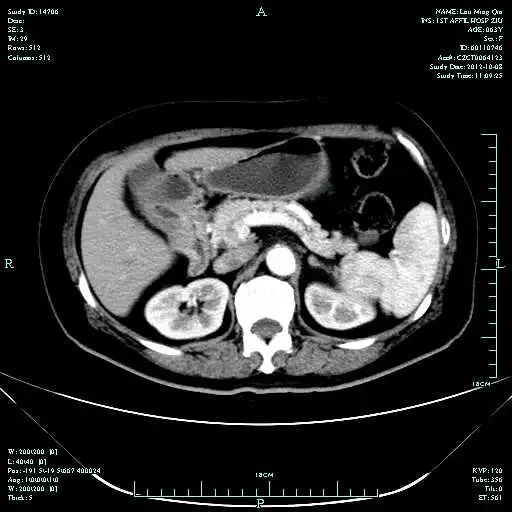

CT-T

CT-H1

MR-H1

影像学检查结果评估:cPD。